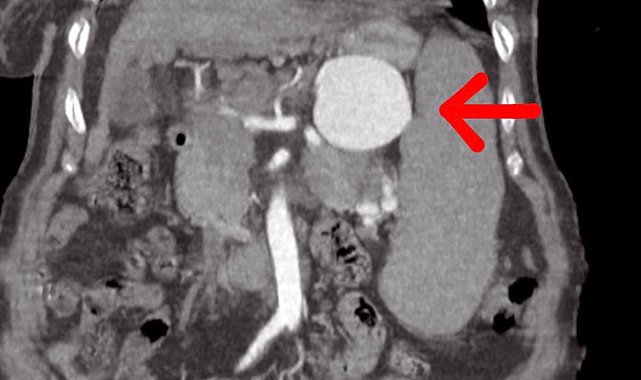

Şırnak'ta, Kalp ve Damar Cerrahisi Uzmanı Op. Dr. Volkan Burak Taban ve Genel Cerrahi Uzmanı Op. Dr. Serhat Binici, dalak arterinde oluşan 7 santimlik baloncuğu yaptıkları riskli ameliyatı başarı ile tamamlayarak 75 yaşındaki ve kronik birçok hastalığı olan Ayşe Ertur'u sağlığına kavuşturdu.Mardin, Diyarbakır, Batman, Siirt, Gaziantep ve Şanlıurfa gibi birçok hastanede dalağının alınması gerektiği ancak dalağının alınması halinde de ameliyat masasından kalkamayacağı söylenen 75 yaşındaki Ayşe Ertur, birçok kronik rahatsızlığına rağmen Şırnak Devlet Hastanesi'nde geçirdiği başarılı ameliyat ile sağlığına kavuştu.Yapılan ameliyat ile ilgili gazetecilere açıklamalarda bulunan Op. Dr. Volkan Burak Taban, hastanın gastroenteroloji kliniğinden kendilerine geldiğini, dalak arterinde ciddi bir anerizma şüphesinden bahsedildiğini söyledi. Değerlendirmeler sonrası ilaç tetkikleri istediklerini belirten Dr. Taban, "Yapılan tomografide teyzemizde dalak arterinde oldukça geniş dev diyebileceğimiz anerizmanın yani baloncuklaşmanın olduğunu gördük. Normalde dalak anerizması diyebilmemiz için baloncuklaşma diyebilmemiz için 20 milim yani 2 santimin üstüne çıkması lazım. Ama gördüğümüzde bizde şaşırdık. Çünkü yaklaşık 7 santimi geçen bir dalak anerizması vardı. Hastanın bu anerizmanın içerisinde tamamen kan dolduğu için her an patlama riski vardı. Allah korusun hastanın hayatını kaybetme riski ile de karşı karşıyaydık. Hasta ile ilgili hemen multidisipliner olarak bir değerlendirme yaptık. Hem gastroenteroloji, hem genel cerrahiden Serhat hocamız, hem radyoloji kliniğimiz ile beraber değerlendirme yaptık. Hastamızın 15 yıldır mücadele verdiği bir karaciğer sirozu da bizim kararlarımızda etkili oldu" dedi."Hasta Şırnak'ta tedavi olmak istedi"75 yaşındaki hastanın Şırnak'ta ameliyat edilmesinin riskli olduğunu ve bu durumu hem hastaya hem de hasta yakınlarına söylediklerini aktaran Dr. Taban, "Hastamız ve yakınları yıllardır hastanemizde tedavi olmak istediler. Bizde hastamıza açık cerrahinin ilk etapta riskli olabileceğini düşündük. Çünkü karaciğer sirozuna bağlı ve diğer hastalıklara bağlı olarak kan değerlerinde inanılmaz derecede bir bozukluk vardı ve cerrahi oldukça riskliydi. Biz öncelikle anjiyo yoluyla kasıktan girerek dalak anerizmasına ulaşıp, dalak anerizmasının içerisini kapatmayı ve dalak damarına bir stent koyarak oradaki anerizmanın patlamasını engellemeyi çalıştık. Anjiyomuz yaklaşık 1,5-2 saat sürdü. Anjiyo salonuna aldık hastamızı, anjiyo sırasında ne kadar uğraşsak ta dalak damarı o kadar genişlemişki kendi etrafındaki damarlar ile beraber döndüğü için dalak damarını bir türlü kateterize edemedik. Dalak damarının içerisine ulaşsak da ardına ulaşamadık. Yaptığımız tekrar değerlendirmesinde hastamızın ameliyat edilmesinin daha doğru olacağını düşündük. Hastamızı açık cerrahi vakasına aldık. Açık cerrahi vakasında genel cerrahi ile birlikte, önce karından ufak bir keski ile girdik. Girdiğimizde karşılaştığımız manzara aslında tomografide gördüğümüz manzaradan veya anjiyoda gördüğümüz manzaradan daha da kötü haldeydi. Dalak damarı anerizmasını onararak hastamızı ameliyattan çıkardık. Ameliyat sonrasında da hastamızın bir yoğun bakım ihtiyacı olmadı. Servise aldık. Bundan sonraki değerlerimize baktığımızda da ciddi bir kan ihtiyacı olmadı. Daha sonraki kontrol kanlarımızda gayet iyi olduğu gözüküyor" dedi.Annesini tedavi etmek için birçok yere götürdüklerini ancak olumlu herhangi bir sonuç alamadıklarını dile getiren Kamil Ertur, "Hocalarımız çok iyi ameliyat geçirdiler. Allah'a çok şükür, ellerine sağlık, onlara teşekkür ediyorum. İyi ki Şırnak'ta böyle hocalarımız var. Diyarbakır, Mardin, Batman, Adana'ya götürdük. Buralarda 'eğer dalak sökülürse yataktan kalkmaz' dediler. Allah'a çok şükür Volkan hoca ve Serhat hocamız böyle başarılı bir operasyon yaptılar" şeklinde konuştu.